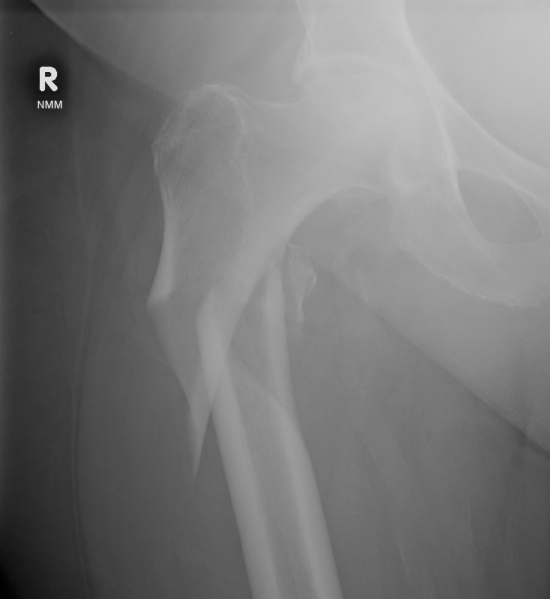

Definition

Fracture below lesser trochanter

Proximal 5 cm femoral shaft

Etiology

Young patients / high velocity injuries

Old patients / osteoporosis

Varus malreduction

Issue

- trendelenberg gait

- LLD

- non union